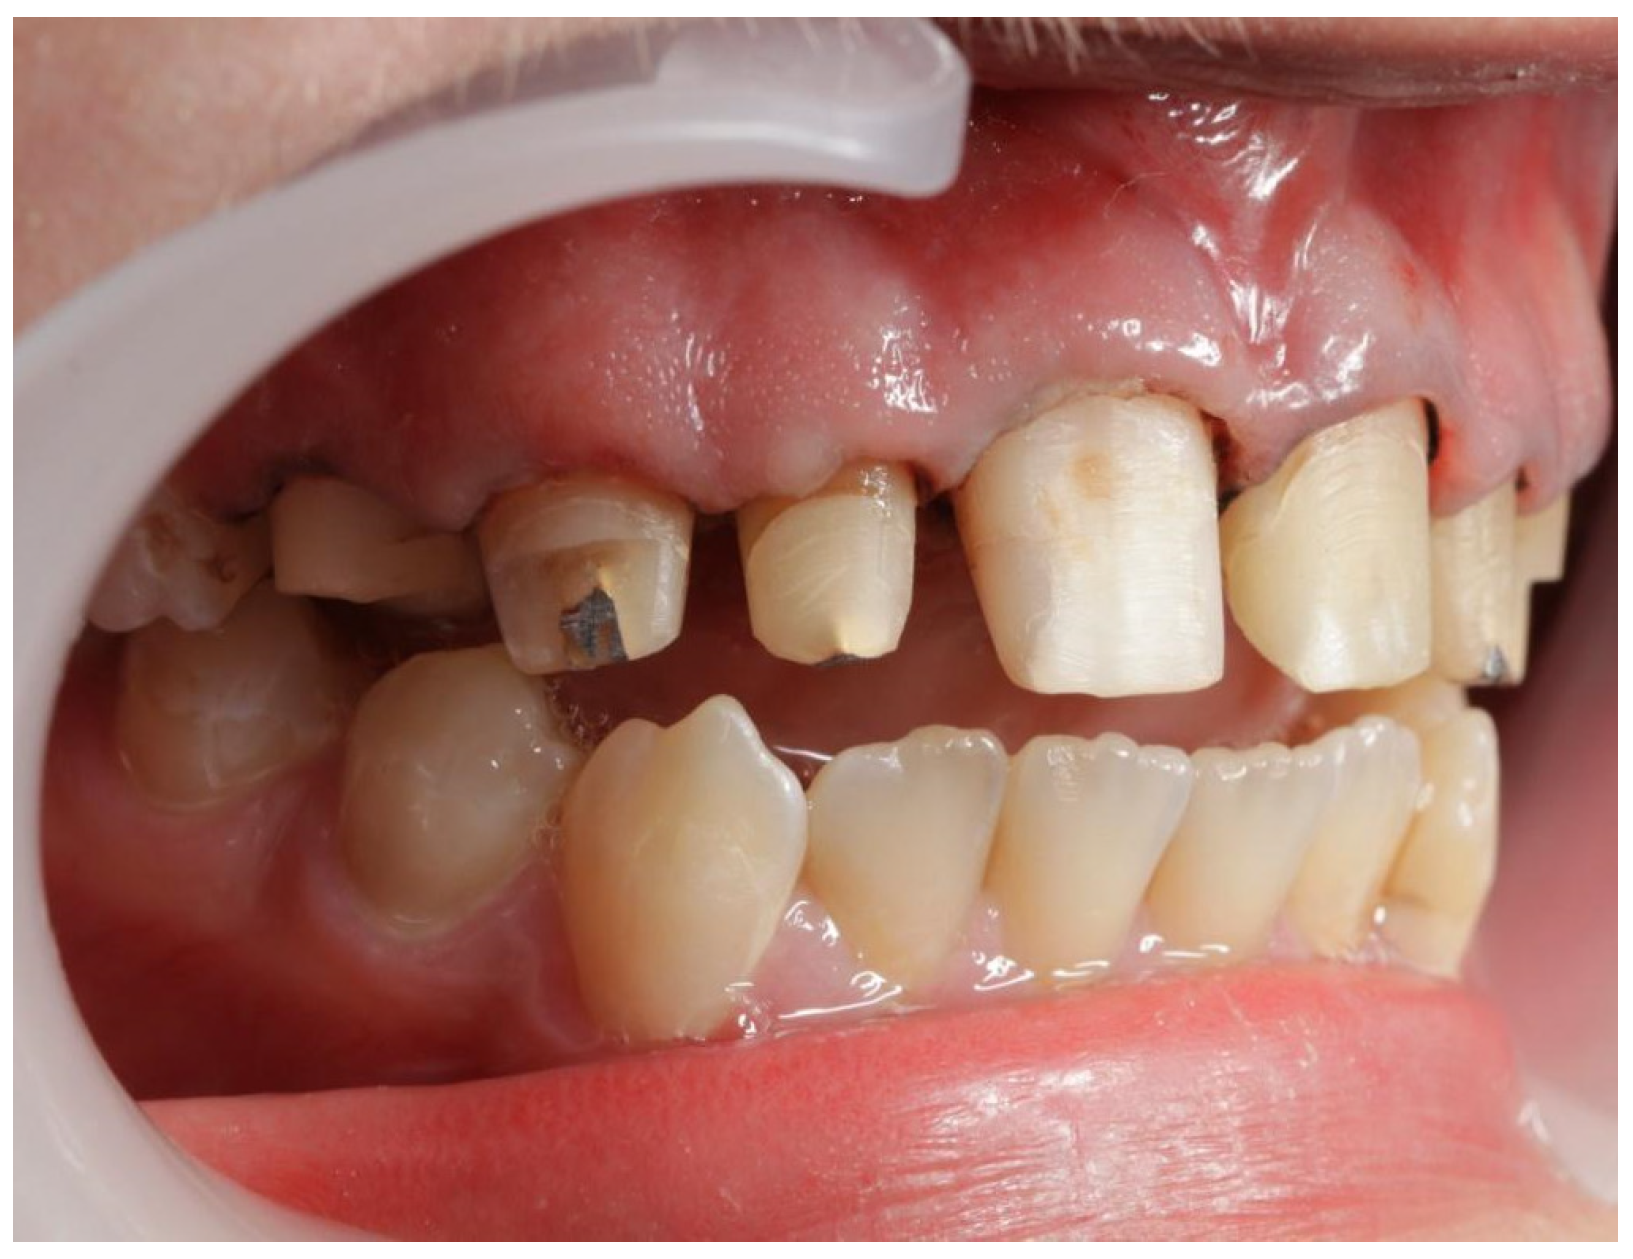

2. Case Report